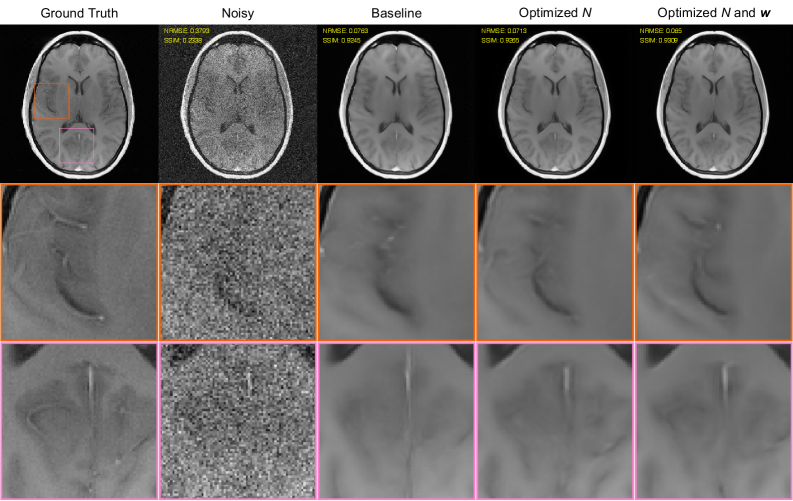

The NRMSE and SSIM values shown in our previous plots can be imperfect measures of image quality and can lack sensitivity to important factors such as spatial resolution and hallucination [kim2018a, antun2020, chan2021]. As a result, it is also important to look closely at the denoising/reconstruction results. Representatitve images are shown for SENSE-TV and U-Net denoising/reconstruction in Figs. 6 and 7, respectively, corresponding to the SNR=2 case. Our subjective assessment of these images suggests that optimizing NN indeed seems to yield meaningful visual improvements in image quality over using the baseline high-resolution acquisition with N=N0N=N_{0}. Specifically, while the denoising/reconstructions in this case have visibly lower-resolution than the ground truth images (as should be expected with NN0N\ll N_{0}), we believe that the resulting images still provide substantially more faithful visual depictions of high-resolution vascular and gray matter structures compared to the images from the high-resolution baseline. On the other hand, while nonuniform averaging produces slightly better NRMSE and SSIM values than uniform averaging, the visual differences between these two approaches are more subtle, and it is difficult to identify a clear winner. This is a common issue in the field, and speaks to the continuing need for better ways of evaluating image denoising/reconstruction performance [kim2018a, chan2021, wang2024, antun2020].

Finally, illustrative results comparing simple linear filtering/apodized reconstruction with optimized acquisition (NN and 𝐰\mathbf{w}) against SENSE-TV and U-Net denoising/reconstruction with the baseline acquisition (unoptimized high-resolution acquisition with uniform-averaging) are shown in Fig. 8. Although the NRMSE and SSIM values in this case suggest that the U-Net offers the best quantitative performance, we personally believe that these metrics are misleading in this case. Instead, we prefer the simple apodized result, which faithfully reproduces many high-resolution vascular and gray matter features that are more difficult to discern in the U-Net and SENSE-TV results. This underscores the importance of designing data acquisition carefully, since even very simple denoising methods with good data acquisition designs can yield major visual advantages over over advanced denoising/reconstruction methods with poorly-chosen data acquisition designs.

Refer to caption

Figure 8: A comparison between advanced denoising reconstruction techniques (SENSE-TV/U-Net) with unoptimized acquisition versus simple linear filtering/apodized reconstruction with optimized acquisition. Results are shown for the SNR=2 case. The left two columns respectively show the ground truth image and the results of simple Fourier reconstruction of the noisy data. The remaining columns respectively show (from left to right): the denoising/reconstruction results obtained with SENSE-TV and the baseline high-resolution uniformly-averaged acquisition, U-Net baseline high-resolution uniformly-averaged acquisition, and apodized reconstruction with optimized nonuniform averaging (i.e., optimized NN and 𝐰\mathbf{w}). This figure otherwise uses the same formatting as Fig. 1 (see the Fig. 1 caption for details).